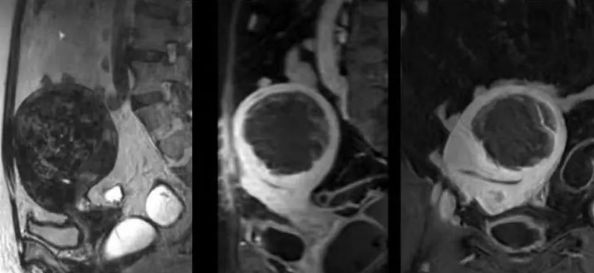

陳寶瑩主任首先給祝女士進行了詳細的盆腔磁共振評估,發(fā)現(xiàn)子宮肌瘤比較大,直徑七公分,類型和位置都適合做磁波刀治療。陳寶瑩主任立即為她制定了個性化治療方案,并為她完成幾項術前檢查。

治療當天,為緩解祝女士的緊張心情,陳寶瑩主任和她進行了充分溝通。術前準備就緒后,治療正式開始了。治療過程中,患者全程清醒,可以及時反饋治療感受。醫(yī)生也即時調(diào)整,確保整個治療安全有效,兩小時后治療順利結束,患者體驗度好。即時評估發(fā)現(xiàn)7公分的子宮肌瘤被消融掉80%,達到了預期目標。祝女士觀察一個小時后,沒有什么不舒服即回家了。